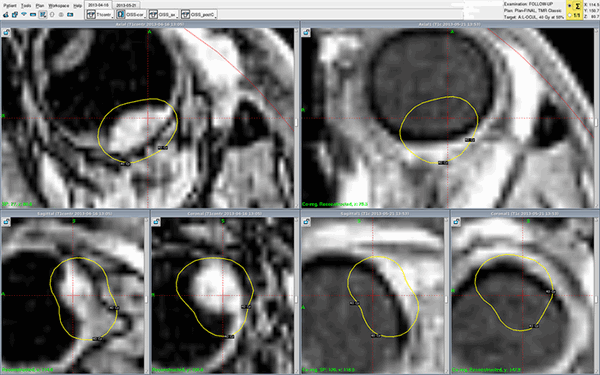

Реальный клинический случай - лечение меланомы хориоидеи Гамма-ножом Gamma-Knife Perfexion в Онкологической клинике МИБС. Снимки МРТ с контрастом (слева - до, справа - после лечения). Меланома хориоидеи на правом снимке, сделанном во время контрольного обследования всего через один месяц (!), не визуализируется - желтые контуры изначального расположения опухоли нанесены для сравнения. Опухоль исчезла. Без операции, с сохранением глазного яблока.